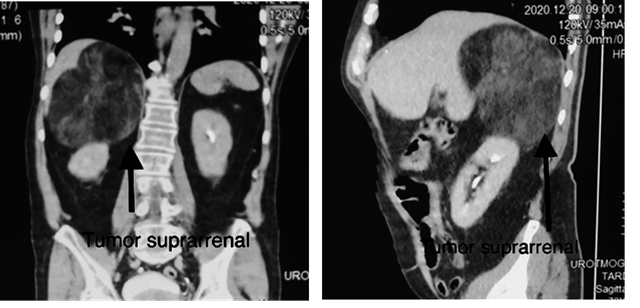

Con estos hallazgos, se decide realizar una tomografía abdominopélvica simple y contrastada en sus 3 fases (arterial, venosa y de eliminación), en la que se evidencia tumor de 15 x 12 cm, dependiente de glándula suprarrenal derecha, que comprime polo superior de riñón derecho, de -20 UH, compatible con mielolipoma suprarrenal derecho gigante, sin alteraciones en otras estructuras, con estos datos de tener una densidad de características grasa totalmente, sin llegar a tener unidades positivas mayor a 10 UH, no fue necesario realizar un estudio de contraste precoz y tardío para evaluar el wash-out, sabiendo que este cálculo se realiza en lesiones con densidades positivas, por las características totalmente benignas, y de componente graso se decide tratamiento quirúrgico ( figura 2).